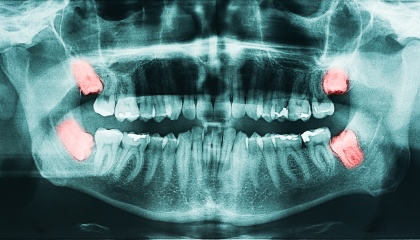

before

after

During your first visit, we will conduct a thorough review of your medical history and engage in a comprehensive discussion about the wisdom teeth removal process. We utilize X-rays to assess the position and condition of your wisdom teeth, enabling us to create a personalized treatment plan tailored to your specific needs and anatomical considerations. This plan will outline the associated costs, timeline, and steps involved in the procedure. We also encourage you to ask any questions you may have; we are committed to addressing any concerns you might have and ensuring you feel fully informed throughout the process.